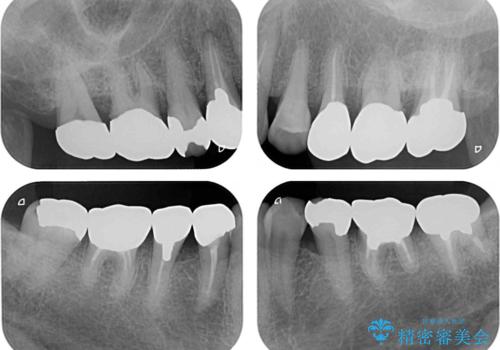

- 奥歯に装着されている銀歯を全て外したいとのことで来院された患者様です。

土台に含まれている金属も含め、奥歯の金属は全て除去し、オールセラミッククラウンやセラミックインレーにて治療することとしました。

- 治療費の目安: 160万円費用は治療当時の料金となります